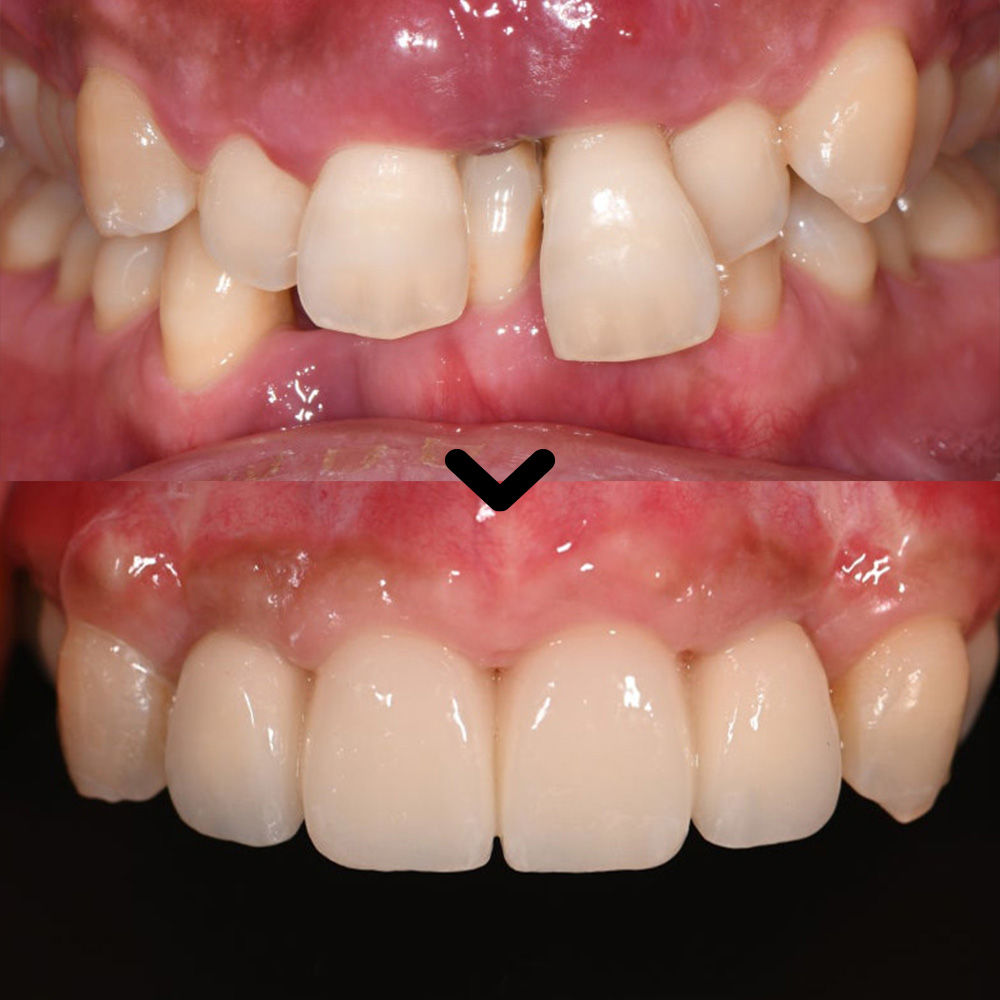

21.07.19 / 23.11.10

참치과에서 진행한

울산임플란트 치료 전후 사진입니다.

환자분께서는 앞니의 비심미적인 요소로 인해

많은 불편함을 겪고 계셨으나,

치료 후 자연스러운 앞니 형태와

심미적인 개선에 대해

매우 만족해 주셨습니다.